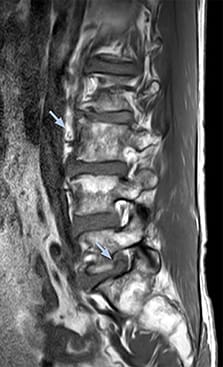

“For example, in sagittal images, when the presence of fat is observed in the intervertebral foramen, it suggests that there is a margin around the nerve. Similarly, the absence of fat indicates that the nerve is being compressed. So, we used to deduce nerve compression indirectly. With NerveVIEW, however, we can observe the condition of the nerves directly, regardless of the presence or absence of fat. We always prefer such direct observation of anatomy over having to make an inference about it.”

“Although symptoms of typical disc herniation and atypical hernia are very similar, the actual site of herniation is different. It is therefore important to characterize the nerve’s condition both inside and outside of the intervertebral foramina. “Conversely, if we see no abnormality in NerveVIEW, we can assume at least that there is no severe condition that requires surgery. Like this, it can help us avoid unnecessary surgery. NerveVIEW can have a tremendous impact in this way.”

“NerveVIEW is really useful for those cases where a nerve disorder is strongly suspected based on the clinical examination but our regular MRI images do not show any findings. These atypical herniations and spinal canal stenosis, occurring in 5% to 15% of the total lumbar herniation/stenosis cases are our main target when using NerveVIEW,” says Dr. Yabuki.

“The intra-luminal signal of veins, especially around the intervertebral space, can be suppressed well with NerveVIEW. As a result, we can easily observe the detailed nerve structure around the posterior ganglion,” he says. “This is why we use 3D NerveVIEW for intraforaminal stenosis and extraforaminal stenosis/herniation (lateral disc herniation). On the other hand, if herniation is suspected to exist inside the dorsal root ganglion (DRG), balanced TFE or ProSet-FFE is applied. NerveVIEW is not suitable for evaluating the median type of herniation.” The SE-EPI DWI-based method for MR neurography works well for large FOV exams like whole-body MRI, but focal examination of nerves is often limited by the attainable spatial resolution (both inplane and slice direction) and geometric distortion. “3D NerveVIEW achieves higher in-plane resolution – close to our other routine spine sequences – and the source images can be used instead of adding a fat-suppressed T2-weighted sequence,” Tanji says.